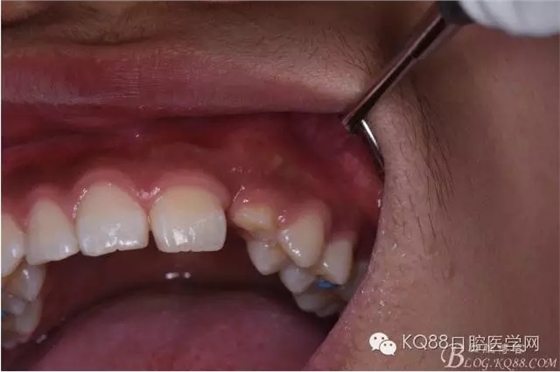

圖6.口內(nèi)觀:63滯留、23未見萌出。